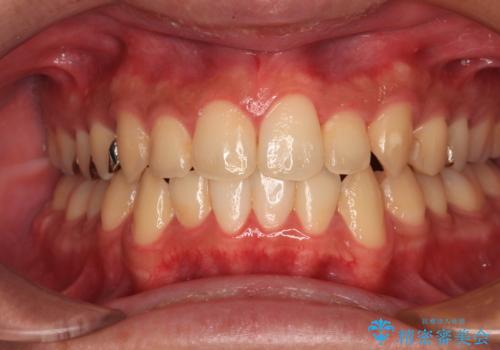

前歯のクロスバイト インビザラインによる矯正治療

- 2年1ヶ月

- 上下のクロスバイトと前歯のデコボコを気にして来院された患者様です。

インビザラインを用い、IPR(歯と歯の間を削る)と歯列全体を拡大させることで、歯並びを整えていくこととしました。